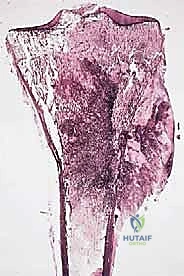

1. ساركوما العظام (Bone Sarcomas)

تنشأ في العظام نفسها وتصيب غالباً الأطفال والشباب. من أشهر أنواعها:

* الساركوما العظمية (Osteosarcoma): الأكثر شيوعاً، تظهر عادة حول الركبة (أسفل الفخذ أو أعلى القصبة).

تتميز هذه الأورام بقدرتها على اختراق الأنسجة المجاورة وتكوين ما يُعرف بـ "المنطقة التفاعلية" (Reactive Zone) أو الكبسولة الكاذبة، والتي تحتوي غالباً على خلايا سرطانية مجهرية. هذا المفهوم البيولوجي هو ما يوجه الدكتور محمد هطيف في تحديد مدى الاستئصال الجراحي.

مبادئ الاستئصال الجراحي: الهوامش الجراحية (Surgical Margins)

الهدف الأول في جراحة الساركوما ليس فقط إزالة الكتلة المرئية، بل استئصالها مع طبقة من الأنسجة السليمة المحيطة بها لضمان عدم ترك أي خلايا مجهرية. تُصنف الهوامش الجراحية إلى:

- الاستئصال داخل الورم (Intralesional): يتم قطع الورم من الداخل. غير مقبول في الساركوما الخبيثة.

- الاستئصال الهامشي (Marginal): الاستئصال عبر الكبسولة الكاذبة للورم. يحمل خطر عودة الورم (Recurrence).

- الاستئصال الواسع (Wide Resection): وهو المعيار الذهبي. يتم استئصال الورم مع طبقة من الأنسجة السليمة المحيطة به (العضلات، العظام). هذا ما يبرع فيه الدكتور هطيف لضمان الشفاء التام.

- الاستئصال الجذري (Radical Resection): استئصال كامل الحيز العضلي أو العظمي الذي يحتوي على الورم.

يتم تقييم مدى استجابة الورم للعلاج الكيميائي (Tumor Necrosis Rate) بعد الاستئصال، وهو مؤشر قوي لفرص الشفاء التام.